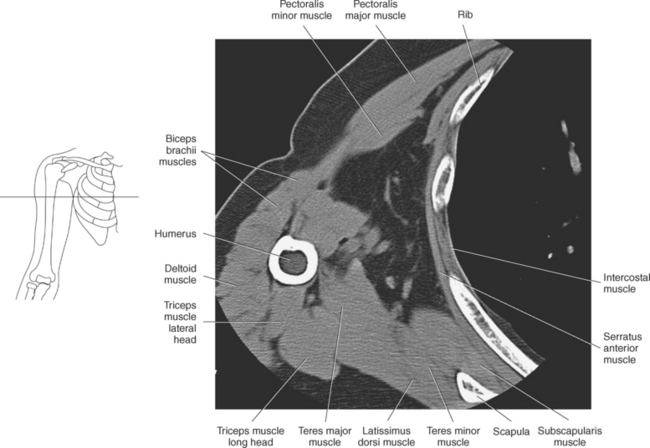

Muscles of the scapula are described in Table 9.2 and demonstrated in Figures 9.34 through 9.52. The large deltoid muscle originates on the clavicle, acromion, and scapular spine to blanket the shoulder joint as it extends to insert on the deltoid tuberosity of the humerus. This powerful muscle forms the rounded contour of the shoulder and functions primarily to abduct the arm (Figure 9.48). The teres major muscle is a flat rectangular muscle that adducts and medially rotates the arm. It extends from the inferior angle of the scapula to the medial aspect or lip of the intertubercular groove of the humerus (Figure 9.49, A). The four remaining muscles, supraspinatus, infraspinatus, teres minor, and subscapularis, closely surround the scapula and compose the rotator cuff (Figures 9.49 through 9.52). The rotator cuff provides dynamic stability to the shoulder joint and allows for adduction, abduction, and rotation of the humerus. The supraspinatus, infraspinatus, and teres minor muscles are located on the posterior aspect of the scapula. The tendons of these muscles insert on the greater tubercle of the humerus. The supraspinatus muscle lies in the supraspinous fossa of the scapula and helps to abduct the arm. The tendon of the supraspinatus muscle is the most frequently injured tendon of the rotator cuff because of possible impingement as it extends under the acromioclavicular joint and continues over the humeral head (Figure 9.49, B). The infraspinatus muscle is a triangular muscle that lies below the scapular spine in the infraspinous fossa. It acts to laterally rotate the arm (Figure 9.49, A). Lying along the inferior border of the infraspinatus muscle is the elongated teres minor muscle, which also acts to laterally rotate the arm (Figure 9.49, B). The subscapularis muscle is the only muscle of the rotator cuff located on the anterior surface of the scapula; its tendon inserts on the lesser tubercle of the humerus (Figures 9.50 through 9.52). The subscapularis muscle acts to medially rotate the humerus. See sequential images through the shoulder (Figures 9.34 through 9.47).

Muscles connecting the upper extremity to the anterior and lateral thoracic walls are demonstrated in Figures 9.34 through 9.47, 9.53, and 9.54 and described in Table 9.3. The pectoralis muscles (major and minor), located on the anterior surface of the chest, primarily aid in the movement of the upper limb (Figure 9.53). The large fan-shaped pectoralis major muscle covers the superior part of the thorax as it spans from the sternum, clavicle, and cartilaginous attachments of the upper six ribs to the lateral aspect or lip of the intertubercular groove of the humerus. Its primary functions are to adduct, medially rotate, flex, and extend the humerus and to assist in forced inspiration. The smaller triangular-shaped pectoralis minor lies beneath the pectoralis major muscle and acts to depress the scapula and assist the serratus anterior muscle in pulling the scapula forward (Figure 9.53). The serratus (sawlike) anterior muscle is visualized on the lateral border of the thorax. It extends from the first rib through eighth rib to the medial border of the scapula. The primary action of the serratus anterior muscle is to protract and stabilize the scapula (Figure 9.54). The subclavius, a small triangular-shaped muscle that spans between the first rib and clavicle, acts to stabilize the clavicle and depress the shoulder (Figure 9.53).

The muscles of the upper arm can be divided into ventral and dorsal groups according to their position. The ventral group contains the biceps brachii, brachialis, and coracobrachialis muscle, and the dorsal group consists of the triceps brachii and anconeus muscles. These muscles are demonstrated in Figures 9.55 through 9.69 and described in Table 9.4.

The triceps brachii muscle is located on the posterior surface of the humerus and is the main extensor of the forearm. Its name triceps is associated with three heads of proximal attachment (long, lateral, and medial). The long head of the triceps originates from the infraglenoid tubercle of the scapula, the medial head originates from the entire dorsal surface of the humerus distal to the radial groove, and the lateral head arises from the dorsal surface and lateral intermuscular septum of the humerus. All three heads join in a common tendon that inserts on the olecranon process of the ulna and the posterior joint capsule (Figure 9.68). The small, triangular anconeus muscle originates on the lateral epicondyle and crosses obliquely to insert on the dorsal surface of the olecranon process, close to the tendon of the triceps brachii (Figure 9.69). It assists the triceps brachii in extension and also provides dynamic joint stability to the lateral joint capsule. For images of the upper arm, see Figures 9.57 through 9.67.